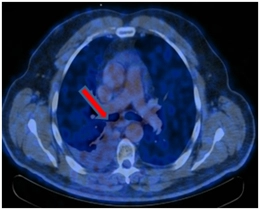

ПЭТ-КТ от 12.01.2017. В правом легком определяется мягкотканое образование метаболическим размером 30×24 мм с кальцинатом в структуре SUVmax=21,36, перекрывающий просвет промежуточного бронха справа сразу за уровнем ответвления среднедолевого бронха с формированием картины «культи бронха» – в бифуркационном лимфатическом узле до 20 мм SUVmax=4,77.